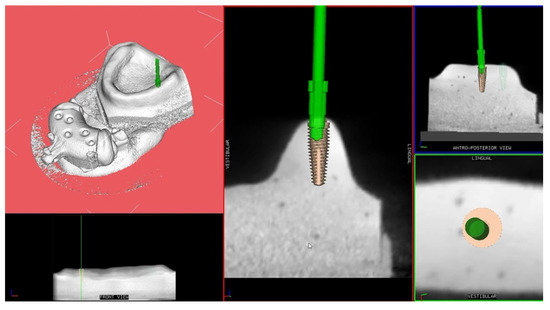

Calibration In Dynamic Navigation Surgery In Implamt